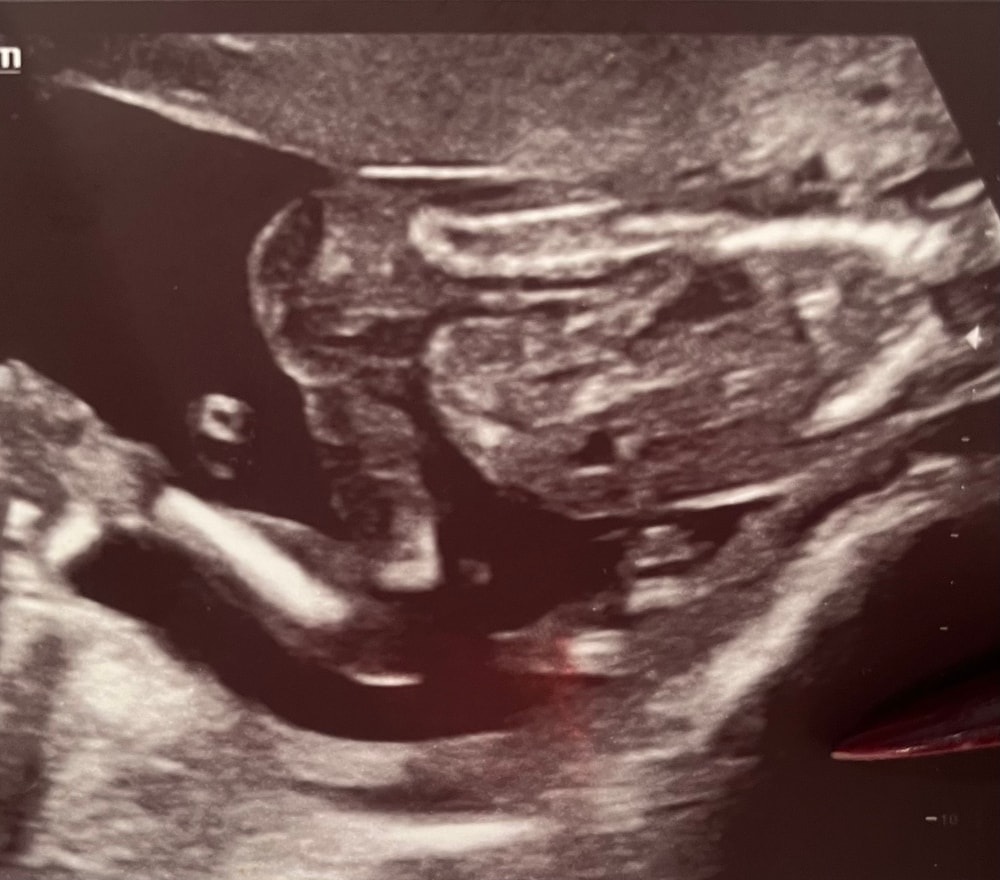

Anastasia в Где же ты, наш малыш? 8 месяцев Пол Планирование пола ребенка 18 недель. Бумажку утеряли с полом. Может кто то разбирается? Посмотрите еще 20 записей на эту тему Отменить Ответить Таро Расклады на зачатие Если то, на что я смотрю, это попка, то вижу девочку 23.04.2025 Ответить Kimiki Девочка 23.04.2025 Ответить Аляля я, конечно, не эксперт, но вижу знакомые наши девичьи черты))) 23.04.2025 Ответить Не могу разобраться Можно Чаты Беременных Выберите чат: Январята-2026 Февралята-2026 Мартята-2026 Апрелята-2026 Майчата-2026 Июнята-2026 Июлята-2026 Августята-2026